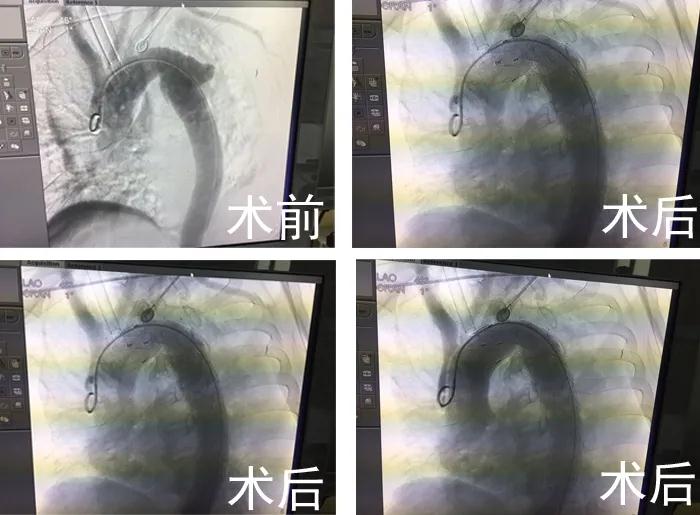

在CCU顏景朋主任、麻醉科陶宏主任的指導下,從股總動脈穿刺插入導管至升主動脈。造影顯示降主動脈左鎖骨下動脈開口遠端約1.8cm,外側(cè)有一破口約1.0cm寬,破口周圍假性動脈瘤形成,通過導入胸主動脈帶膜支架精確定位到左鎖骨下動脈后緣,然后釋放,再次造影,顯示破口封堵成功,手術(shù)順利結(jié)束。